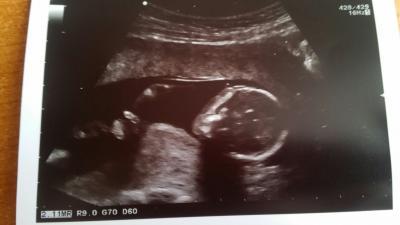

Hallo ihr Lieben August-Mamis :) Ich bin erst gerade auf euer Forum gestoßen und habe gleich eine Frage an euch :) Ich bin in der 15. SSw. und war gerade bei der FÄ. Unserem Baby geht es super und es wiegt schon 104g. Zum Geschlecht konnte sie noch nichts sagen, sie schaute dann zwar einige Zeit zwischen die Beine, doch sie meinte, es sei zu früh. Dann sagte sie noch, bei Mädchen können die Schamlippen in diesem Zeitraum auch noch größer sein. Für uns ist es ganz egal, was es wird, wir freuen uns wirklich über beides. Natürlich hätten wir es aber gerne schon erfahren, damit wir uns schon drauf einstellen können :) Jetzt habe ich nochmal die US-Bilder angesehen und auf dem letzten Bild (ich weiß nicht, welche Perspektive das genau ist), sieht man links irgendetwas kleines hinaufstehen. Ich weiß, dass ihr auch keine Experten seid, aber vielleicht kennt sich schon jemand besser aus mit US-Bildern, als ich? Könnte das nicht ein Schniepelchen sein? Oder eher Nabelschnur oder ein Händchen? Wenn das ein Schniepelchen wäre, dann wäre es wohl eindeutig, oder? Dann hätte sich vielleicht doch etwas sagen können? Tut mir leid, dass ich gleich mit solch einer ausführlichen Frage komme, ich bin einfach so aufgeregt :) Ganz liebe Grüße!

Bild zu Neu hier und gleich eine Frage an euch, zurück vom FA :) - Forum für August - Mamis

Herzliche Willkommen! Schön dass du auch zu uns gefunden hast! Ich glaube nicht dass das was man da sieht ein Schnippel ist, dafür ist es zu nah am Brustkorb und auch zu groß!!! Ich tippe eher auf eine Hand!

vielen Dank für eure Antworten :) ja, wahrscheinlich warte ich einfach noch. aber wisst, ihr, was ich da links meine? Ich mache mal nen Pfeil hin :-)